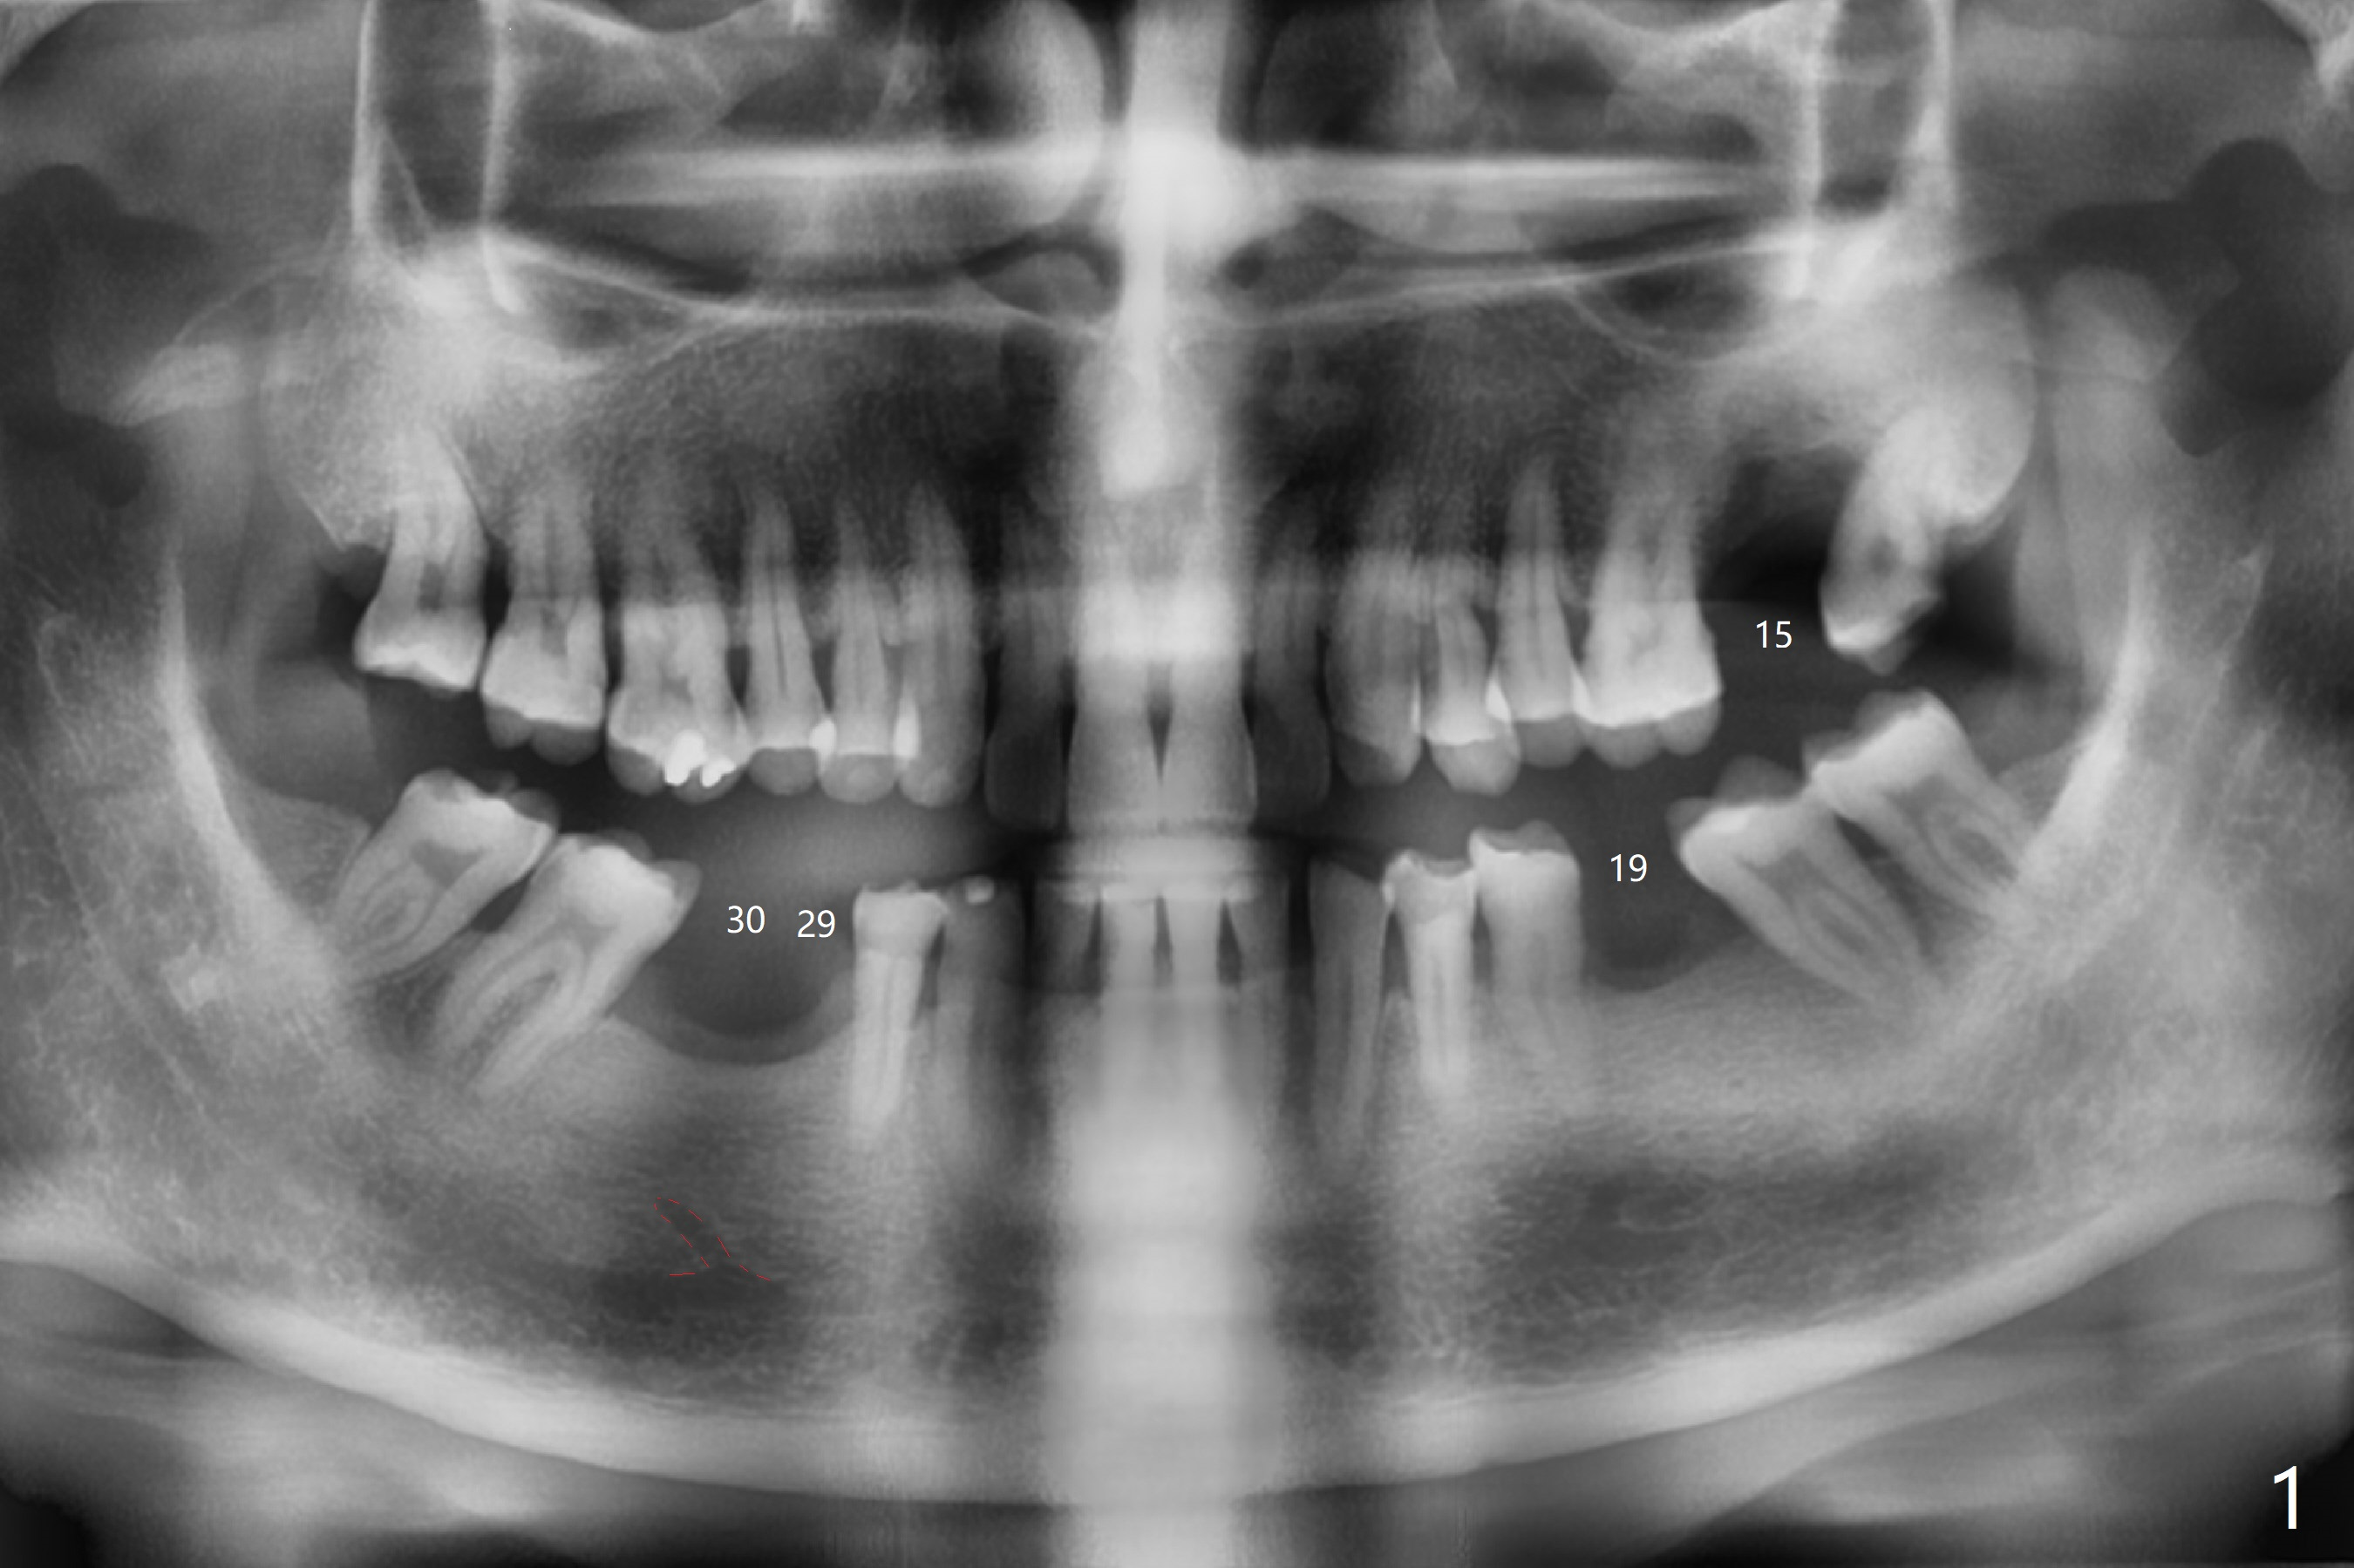

A 62-year-old man with more than 10-year-old lower RPD requests implant at #15 with history of tooth fracture (Fig.1). Guided surgery is planned at #15 (Fig.2).

The patient would like to have implants to replace the lower RPD if the 1st surgery turns out to be successful. Due to the presence of the Mental Loop (Fig.1 red dashed line) and thin bone at #29 and 30 (Fig.3,4), 1-piece implants seem to be a good option. A 2-piece implant can be placed at #19 (Fig.5). After cementation of #15 implant crown, reanalysis of CT reveals that a 3x12 mm 1-piece implant is more appropriate at #19 with a space less than a premolar (Fig.6). With 2 of narrow short implants at #29 and 30, violation of the Mental Loop is less likely to happen than a single one in the middle of the edentulous area (Fig.7).